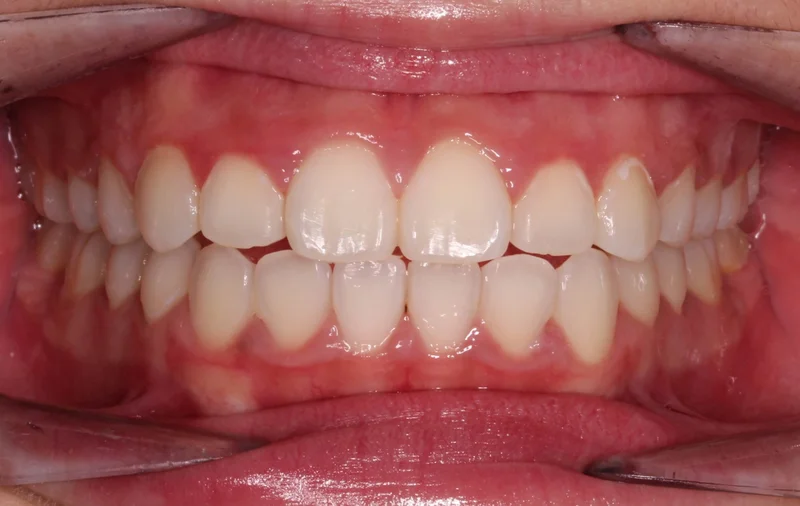

Center Bite - After Treatment

After